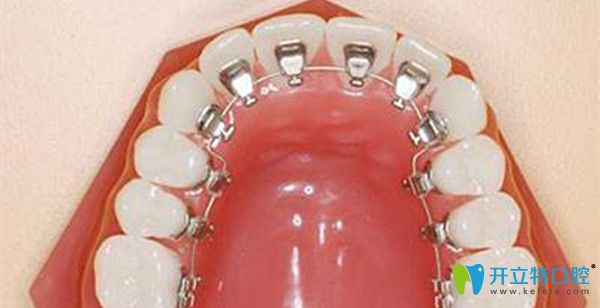

舌側(cè)保持器的優(yōu)缺點